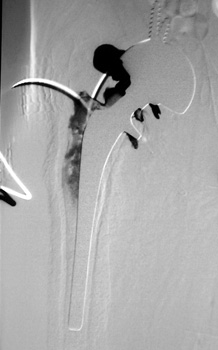

Dry tap secondary to large greater trochanteric bursa, 20

gauge spinal needle placed in bursa under fluoroscopic guidance

Scar with focal area of drainage. Dry tap secondary to large greater trochanteric bursa with

sinus tract draining to skin